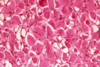

What is “Sulfur granules”

Where it is found?

In which infection?

color?

colonies of bacteria (o Actinomyces israelii

o Actinomyces viscosus)

found in suppuration (pus) which means Suppuration (pus) is dead tissue, bacteria, dead white blood cells, and other products of tissue breakdown..

Sulfur granules found in Actinomycoses

yellow in color